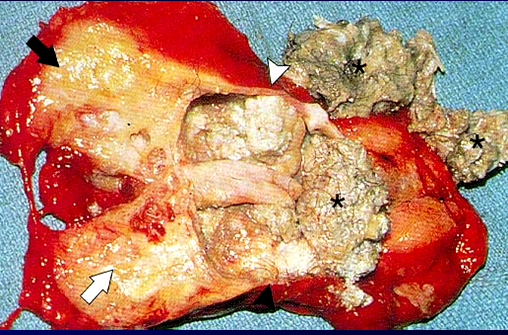

Kəskin mediastinit şübhəsi olan xəstə təcili xəstəxanaya yatırılır, diaqnoz qoyulan kimi aktiv dəstək, antibiotikoterapiya başlanılır və cərrahi müalicə həyata keçirilir. Kəskin mediastinitin müalicəsində cərrahi müalicə əsas tədbirdir və iki məqsədlə yerinə yetirilir: irinliyin sanasiyası-drenajı və səbəbin aradan qaldırılması (Şəkil 12).

Şəkil 12. Divararalığının drenajı

Sanasiya-drenaj üçün divararalığına yuxarıdan, transsternal, transtorakal yollarla müdaxilə etmək olar. Səbəbi aradan qaldırmaq üçün edilən əməliyyatlar səbəbdən asılı olaraq dəyişir.